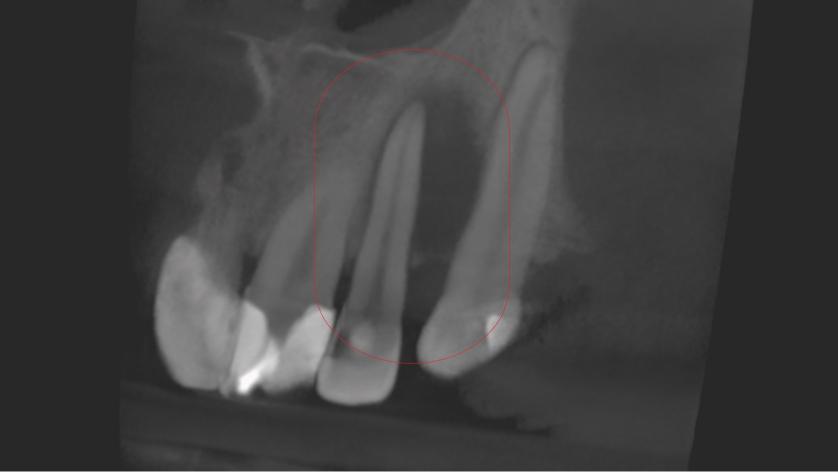

Leczenie kanałowe jest leczeniem skutecznym. Prawidłowe leczenie kanałowe sprawia, że ząb przestaje być ogniskiem zakażenia, a tkanki wokół goją się. Wyleczenie zęba powoduje, że przyczyna choroby tkanek około zębowych [na RTG widzimy jedynie chorobę kości] zostaje usunięta. Eliminacja przyczyny choroby umożliwia gojenie się zmian chorobowych.

Na poniższych zdjęciach RTG – WIDAĆ GOJENIE ZMIAN ZAPALNYCH KOŚCI.

W naszej poradni leczenie prowadzą lekarze endodonci, doświadczeni w leczeniu kanałowym, jakość leczenia podnosi stosowanie mikroskopu oraz kontrola radiologiczna. Nasz tomograf umożliwia uwidocznienie kanałów oraz sprawdzenie jakości ich wypełnienia.